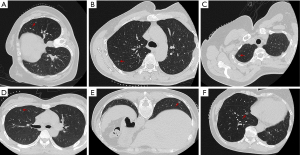

We performed a retrospective cohort study of 145 patients with pulmonary nodules located in challenging anatomical regions, where percutaneous lung puncture was deemed unfeasible. The study was conducted in accordance with the Declaration of Helsinki and its subsequent amendments. The study was approved by the ethics committee of the First Affiliated Hospital of Soochow University (No. 2025376). All patients participating in this study signed informed consent. These patients underwent Uni-port VATS resection with preoperative localization at the First Affiliated Hospital of Suzhou University between September 1, 2022, and September 30, 2024. All patients underwent preoperative localization using either ENB-guided ICG marking or CT-guided hook-wire placement prior to Uni-port VATS resection. Of these, 42 patients received ENB-guided localization, while 103 patients underwent CT-guided hook-wire localization. The inclusion criteria were as follows: (I) patients aged 18 years or older; (II) pulmonary nodules confirmed by thin-slice high-resolution computed tomography (HRCT) and deemed suitable for VATS resection following evaluation by a multidisciplinary lung neoplasms committee; (III) pulmonary nodules measuring less than 30 mm in diameter; (IV) nodules that could not be accurately localized through intraoperative visual inspection or manual palpation; (V) patients who underwent preoperative localization using either ENB combined with ICG injection or CT-guided hook-wire placement; and (VI) pulmonary nodules located in anatomically challenging regions (Figure 1), including the lung apex, interlobar fissures, areas adjacent to the diaphragm or mediastinum, proximity to major vessels, the posterior aspect of the female breast, or regions obscured by the scapula. Patients were excluded if (I) nodule maximum diameter >30 mm; (II) the occurrence of distant organ metastasis; (III) severe coagulation disorders, severe cardiopulmonary dysfunction, and severe infectious diseases; (IV) using other positioning methods instead of hook-wire localization or ENB-guided localization (Figure 2).

Challenging anatomic areas for hook-wire localization

The distribution of challenging nodule locations showed lobar fissures as the most common site [ENB: 38.1% (16/42) vs. CT-guided: 39.8% (41/103), P=0.85], followed by near diaphragm [ENB: 23.8% (10/42) vs. CT-guided: 28.2% (29/103), P=0.59], anterior to scapula [ENB: 26.2% (11/42) vs. CT-guided: 19.4% (20/103), P=0.37], retromammary in females [ENB: 9.5% (4/42) vs. CT-guided: 10.7% (11/103), P>0.99], lung apex [ENB: 9.5% (4/42) vs. CT-guided: 3.9% (4/103), P=0.34], and near mediastinal vessels/spine [ENB: 4.8% (2/42) vs. CT-guided: 12.6% (13/103), P=0.27], with no statistically significant differences observed between localization methods for any anatomical location (Table 2).